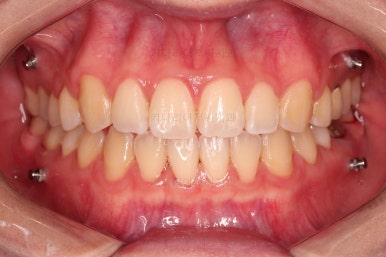

1. 처음 내원 시의 입안의 모습

부산치아교정잘하는곳 키다리아저씨치과에 처음 내원하셨을 당시의 입안 모습입니다.

얼핏 보면 많이 삐뚤어지지는 않은 편인데, 눈에 바로 띄는 앞니가 뻗쳐 있으면서 획 돌아있는데요. 정렬이 필요한 상황이었습니다.

어금니쪽은 많이 삐뚠 편은 아니었으며, 윗니 앞니가 많이 앞으로 뻗쳐 있는 상태였습니다.